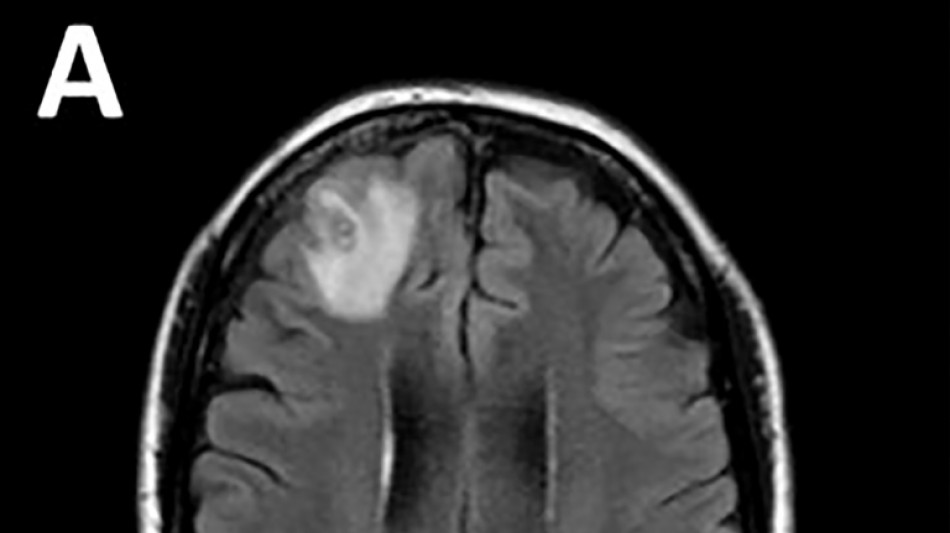

Médicos australianos hallan por primera vez una lombriz parásita en el cerebro de una mujer

Médicos australianos hallan por primera vez una lombriz parásita en el cerebro de una mujer / Foto: Handout - Universidad Nacional Australiana/AFP

Desconcertados, los médicos realizaron una resonancia magnética a una mujer australiana de 64 años después de que comenzara a sufrir lapsos de memoria y notaron una "lesión atípica" en el frente de su cerebro.

Era una lombriz de ocho centímetros llamada Ophidascaris robertsi, que según investigadores son parásitos comunes en canguros y pitones diamantina pero no en humanos.